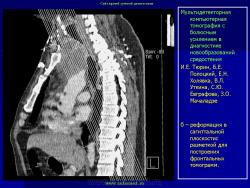

Средостение.  "Опухолевый рост".